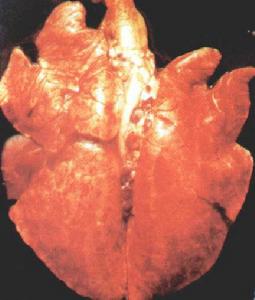

老化肺臟1.老化肺臟具有作為啟動老年人器官功能不全的病理生理基礎。隨著年齡的增長,肺臟老化,功能下降。因此同樣的外界刺激導致老年人的肺部疾患較中青年嚴重,難治療,預後差。

老化肺臟老年人由於動脈粥樣硬化、器官老化和慢性病的影響,循環系統的代償能力明顯減退,在低灌注或感染等因素的作用下,大量細胞因子(TNFα、IL等)及炎症介質(PGE、TXA2等)的釋放,致微血管舒縮功能紊亂,血流淤滯,血細胞聚集及微血栓形成,最終引起組織細胞缺血、缺氧。

老化肺臟2、循環功能的維護和治療(1)密切監測血壓、心率等生命體徵變化及周圍循環狀態。(2)維持有效血容量,嚴格記錄液體出入量,動態監測中心靜脈壓。(3)加強抗心衰治療,可聯合套用洋地黃、利尿劑、ACEI和受體阻滯劑。(4)急躁糾正低血壓計低灌注狀態。可給予多巴胺0.5—3.0μg/kg?min,或多巴酚丁胺2.5—10μg/kg?min,處理好低血容量與心衰的矛盾。